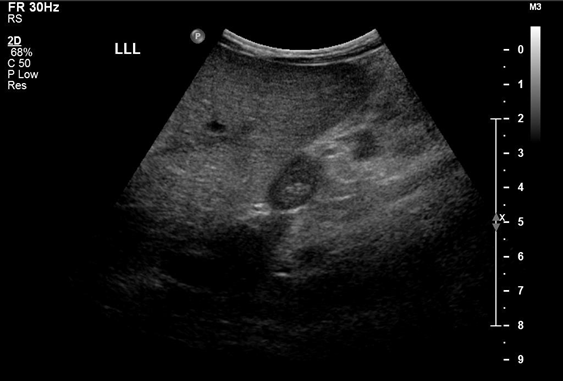

Renal candidiasis presents with candiduria and ultrasonographically demonstrated renal parenchymal lesions, often without symptoms related to renal disease.

For invasive disease, investigation for a deep tissue focus of infection is important- in the form of echocardiogram, renal or abdominal ultrasound. Central venous catheters may need to be removed when feasible in HIV-infected children with candidaemia. The treatment of choice for invasive disease in HIV-infected children depends on severity of disease, previous azole exposure, and Candida isolate obtained (if known). Recommended duration of therapy for candidaemia is 14 days after documented clearance from the blood.